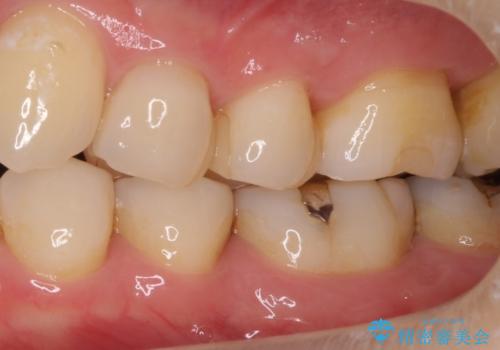

- 左下の銀歯の横から小さい虫歯になっていたため治療しました。

自費のインレーは、ゴールドかセラミックが選択可能です。

今回は患者様のご希望によりセラミックとなりました。